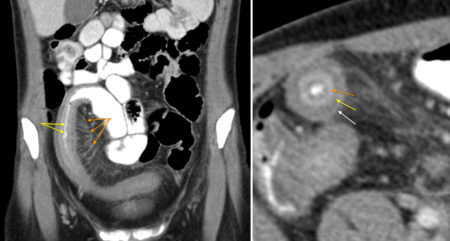

• CT

• 주로 말단 회장부를 침범하는 segmental 병변

• 장벽 두께 증가 및 점막하 부종으로 인한 target sign (yellow arrow)

• Comb sign: 장 주위의 fibrofatty proliferation으로 인해 mesenteric vessel이 확장되고 넓게 퍼진 소견 (orange arrow)